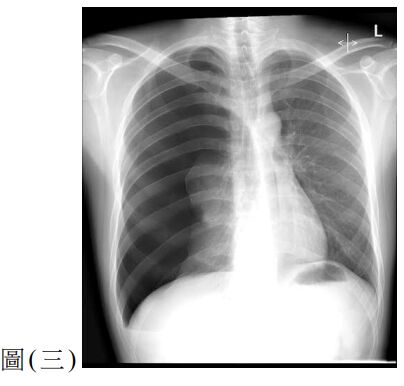

12. 一位 25歲男性因呼吸困難至急診就醫,主訴2天前工作撞擊到右側胸部,胸部X光檢查如圖(三),下列處置何者較適當?

(A) 立即給予右側胸管置入引流 (B) 觀察呼吸困難狀況並給予肌肉鬆弛劑 (C) 立即安排胸腔鏡手術治療 (D) 安排胸部電腦斷層檢查確立診斷